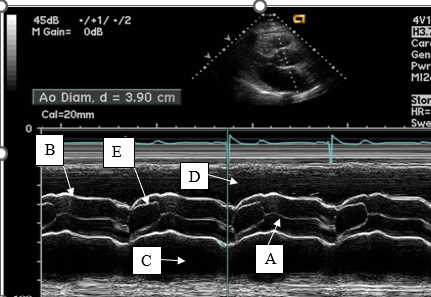

Letters A and C represent these waveforms.

What is a- rapid or early filling and c - atrial systole or atrial kick?

Letter E represents this aortic valve cusp and it's position during systole.

What is the right coronary cusp in the open position?

This line represents aortic valve closure on m-mode.

What is A?